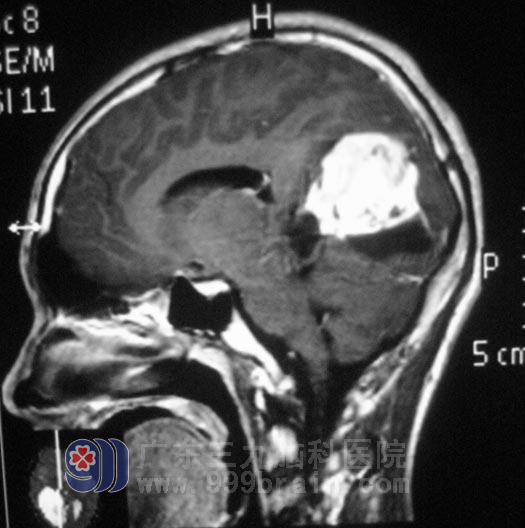

可偏偏是越怕有事,就越来事。一年前王阿姨的儿子因为鼻息肉大出血行息肉切除手术。四天前又出现头痛,伴恶心呕吐,精神食欲差,进食后呕吐加重,在当地人民医院头颅CT检查,结果提示“右侧大脑镰占位性病变,考虑脑膜瘤”。两口子当时就瘫在了地上。

慕名来到广东三九脑科医院,综合神经外科 鲁明主任经过检查后,初步考虑为星形细胞瘤。2月24日,鲁明主任主刀在全麻下行右侧枕叶占位性病变切除术,术中显微镜下见粉红色肿瘤,质地较韧,血供丰富,肿瘤主要位于枕叶,内近大脑镰,予肿瘤全切。术后儿子的精神症状逐渐好转,头痛头晕症状明显消失,未再出现呕吐。全家人如释负重,还有些隐隐担心。术后病理结果为:肥胖性星形细胞瘤。